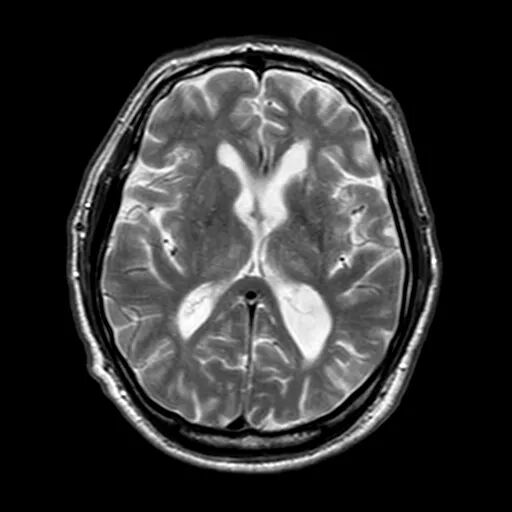

颅脑磁共振+头颈MRA:未见新发梗死;右侧颈内动脉C1段重度狭窄。